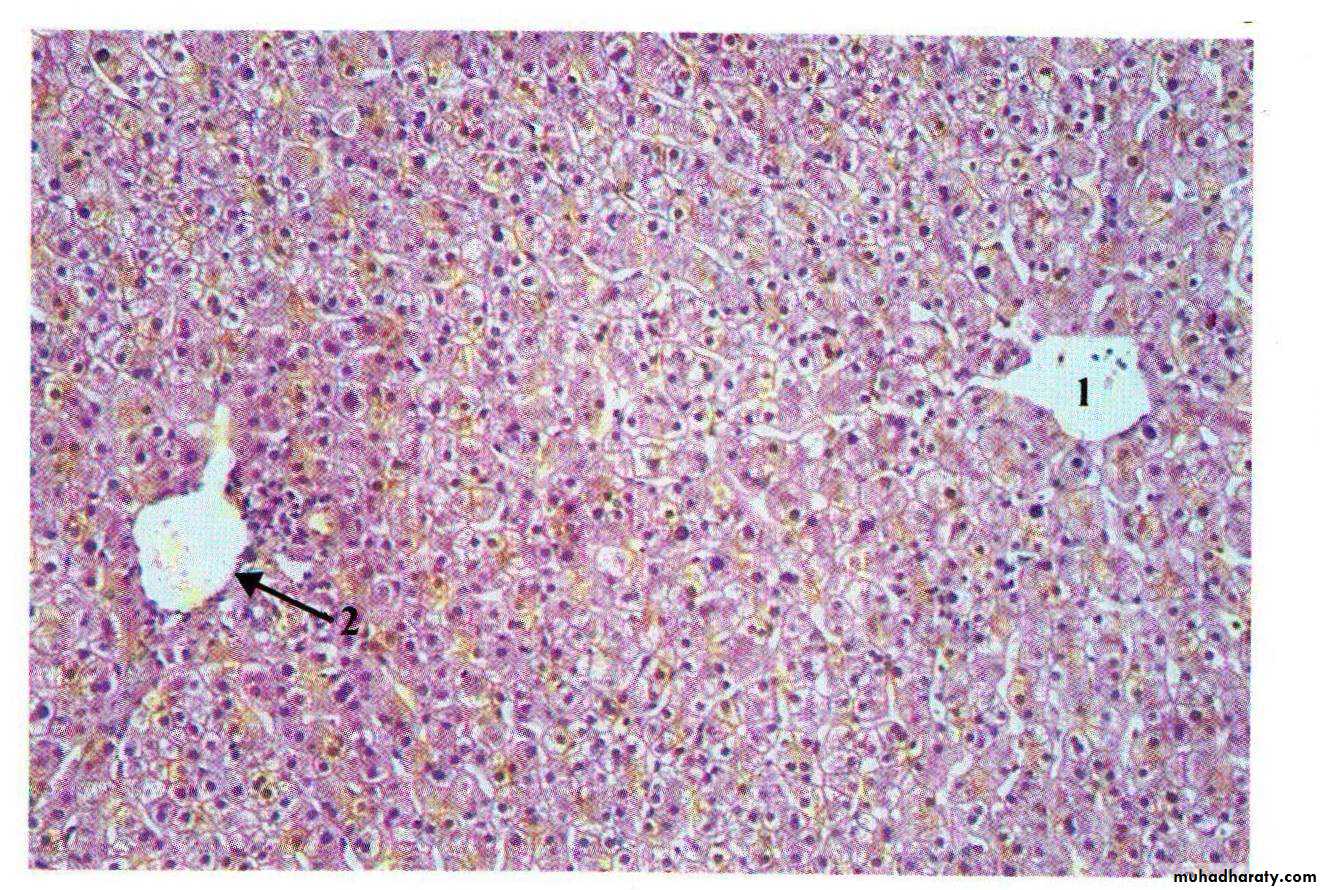

• Pathology

• Fatty liver• Alcoholic hepatitis – Mallory’s hyaline